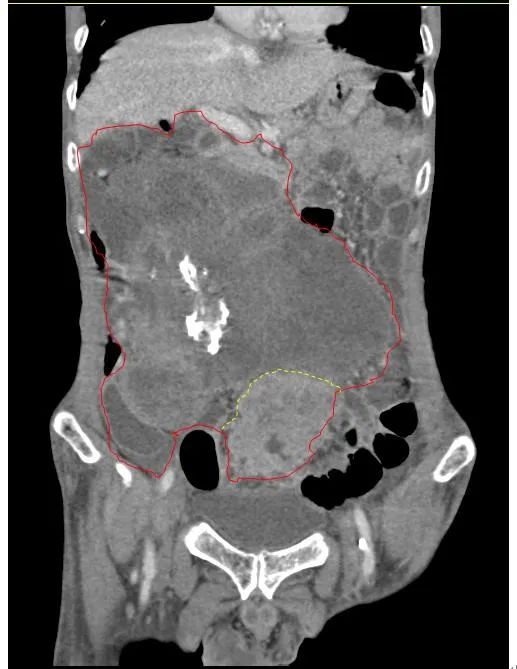

患者王大爺,男,72歲,發(fā)現(xiàn)腹腔腫物10余年,近兩年來患者雙下肢乏力、貧血,依靠間斷輸血維持著正常生活,出現(xiàn)頭昏,行動困難,腹部疼痛及便血慕名來我院就診。入院后查體評估患者年齡大,體質(zhì)差,嚴重貧血,肺部感染及腸梗阻征象,腹部增強CT檢查提示腹膜后巨大腫瘤,長徑超過30厘米,占據(jù)大部分腹腔,并可能存在雙原發(fā)腫瘤。

苗滿園腫瘤外科團隊在麻醉科/手術室的緊密配合下為該患者進行手術,術中發(fā)現(xiàn)腫瘤巨大,幾乎占據(jù)了整個腹腔,從左側(cè)向右腹腔延伸,向上將肝、腎擠向膈下,向左將胃及小腸擠向左上腹,向下深達盆腔內(nèi),包繞下腔靜脈、腸系膜上動脈等大血管及輸尿管,回盲部及回腸也受侵犯。手術難度巨大,風險極高。團隊憑借著高超的手術技能和精準的手術預案沉著應對,迎難而上,應用高頻電刀、超聲刀、切割縫合器等先進設備,耗時近5小時為患者切除了巨大腹腔腫瘤,并聯(lián)合右半結(jié)腸切除,術中出血僅50ml。術后病理為腹膜后巨大平滑肌瘤+回腸腺癌。